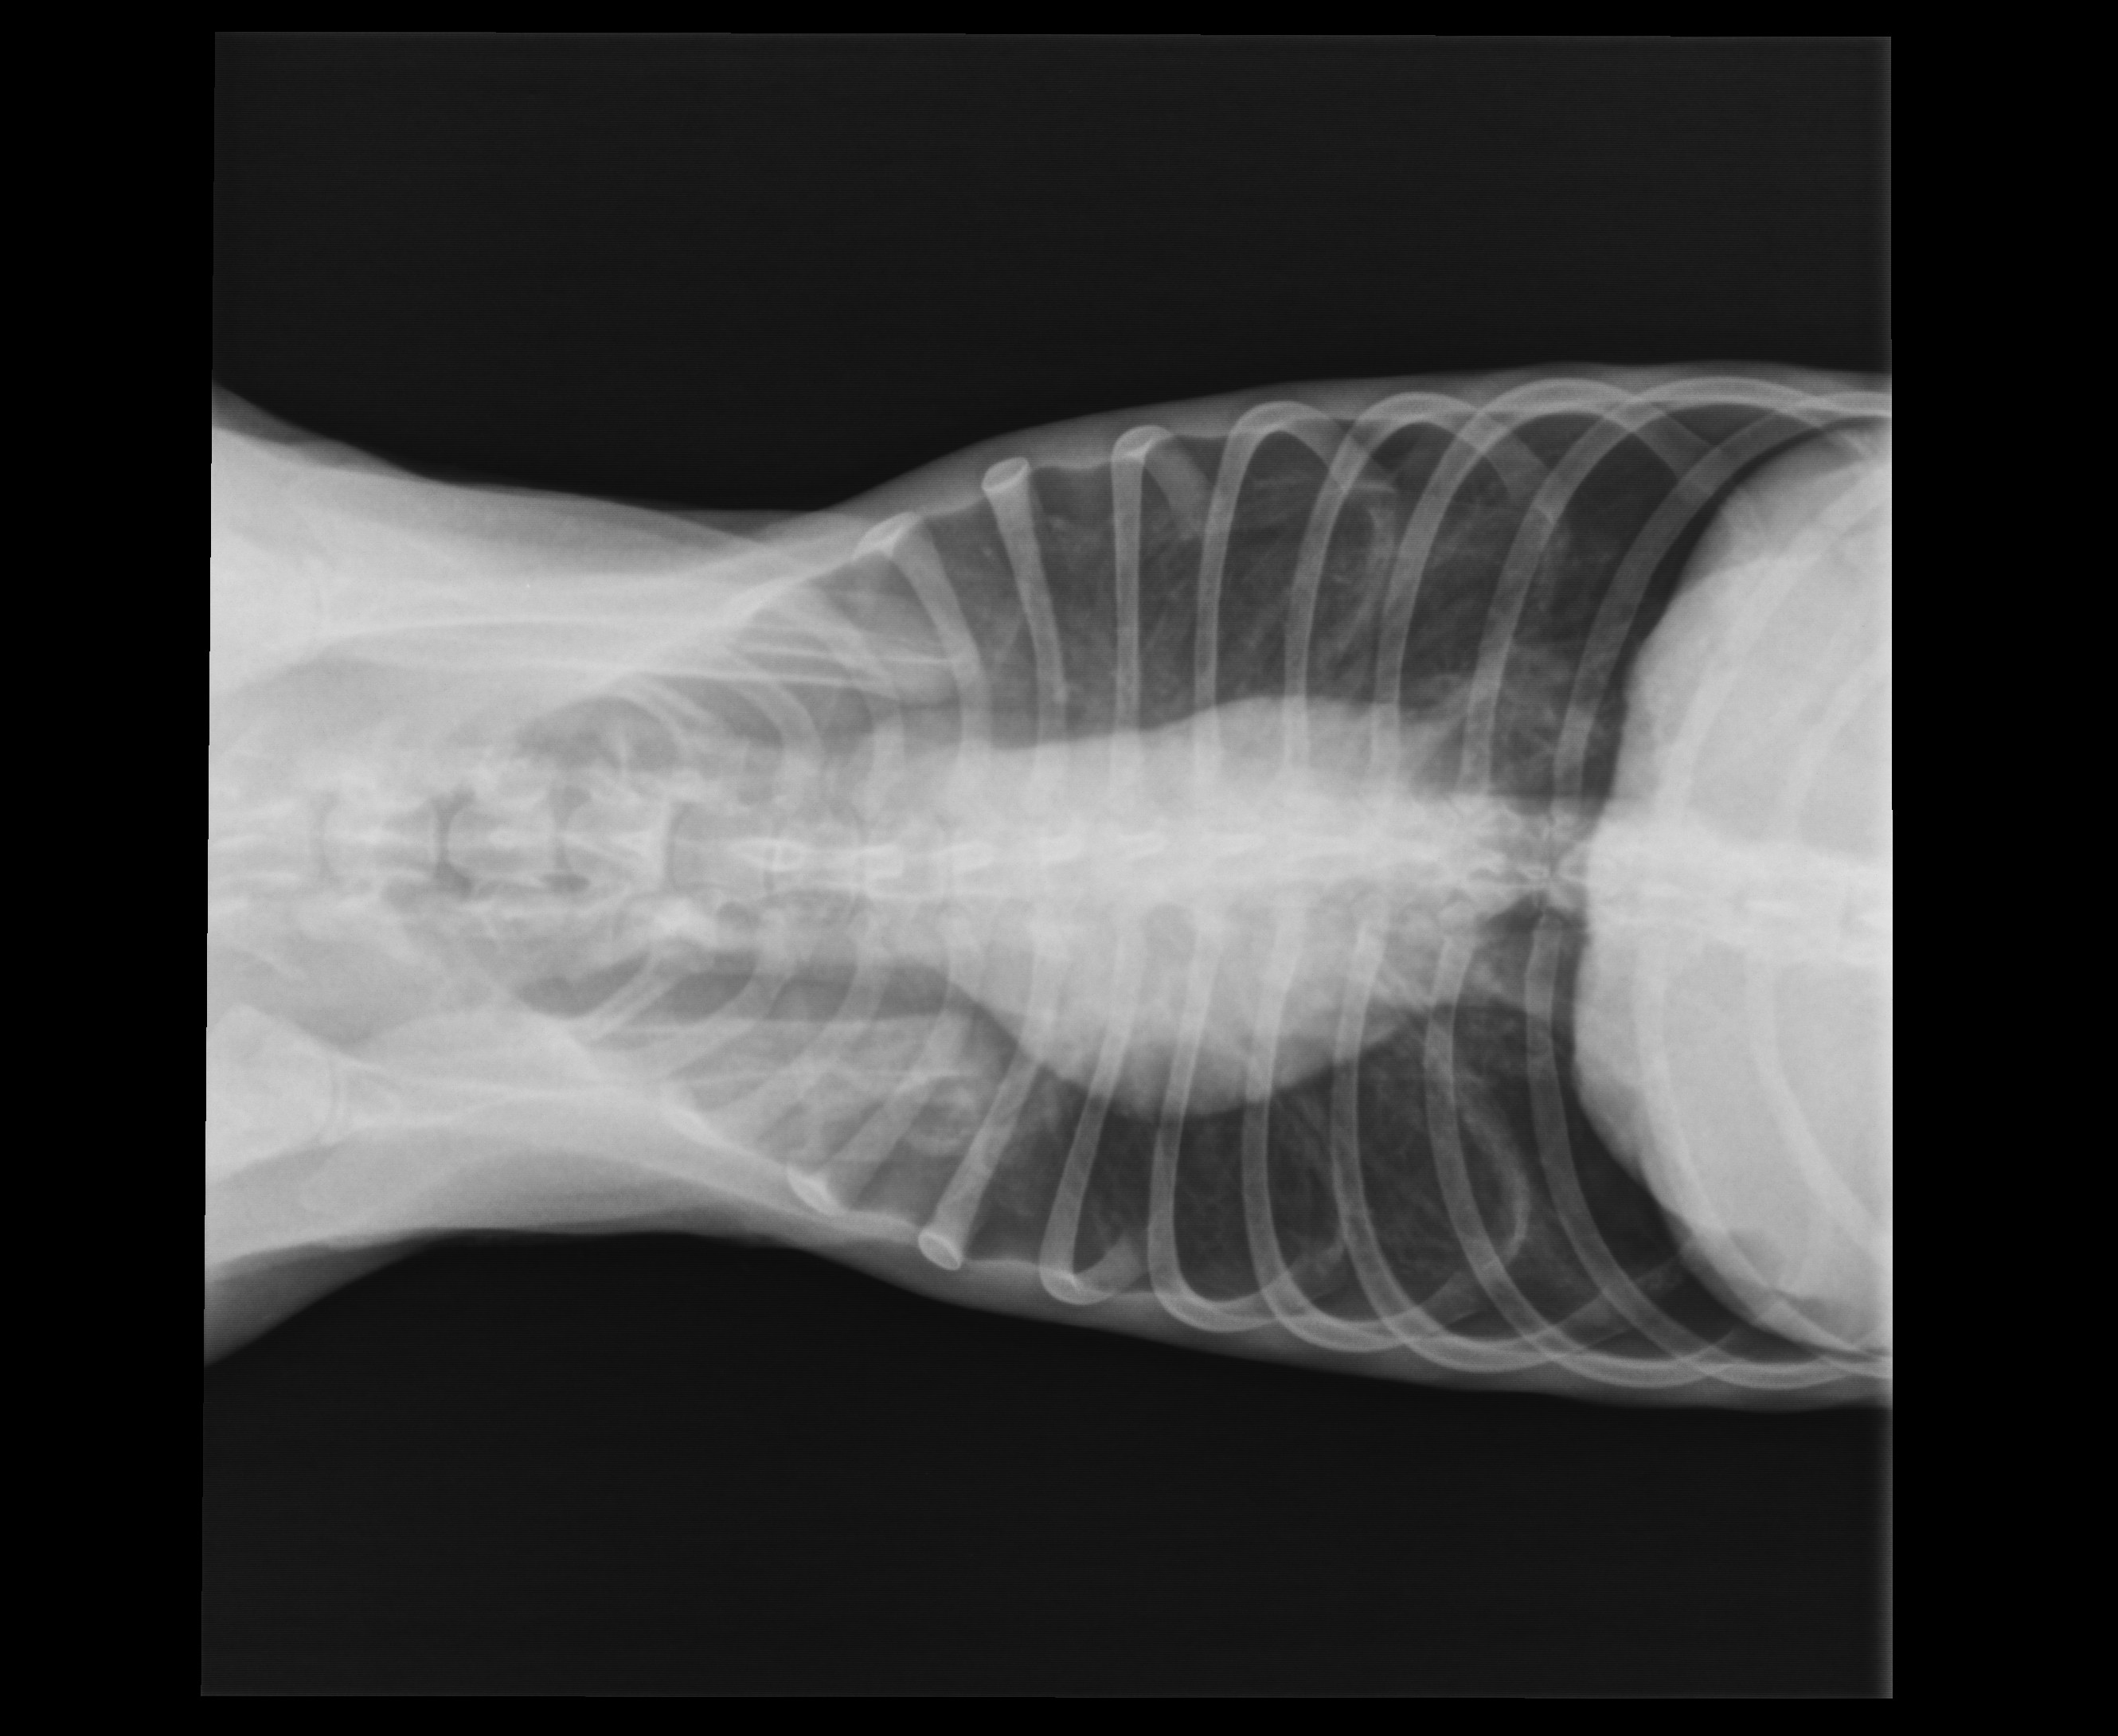

A SEAN le han hecho analitica y radiografias.

Radiografias

Se observa que tiene los pulmones perforados y el torax lleno de aire (de alli la respiración dificultosa) y para eso lo único es reposo.

Tiene la cadera fuera de su sitio y será necesario operación para cortar la cabeza del femur. Estas son las radiografías de SEAN: